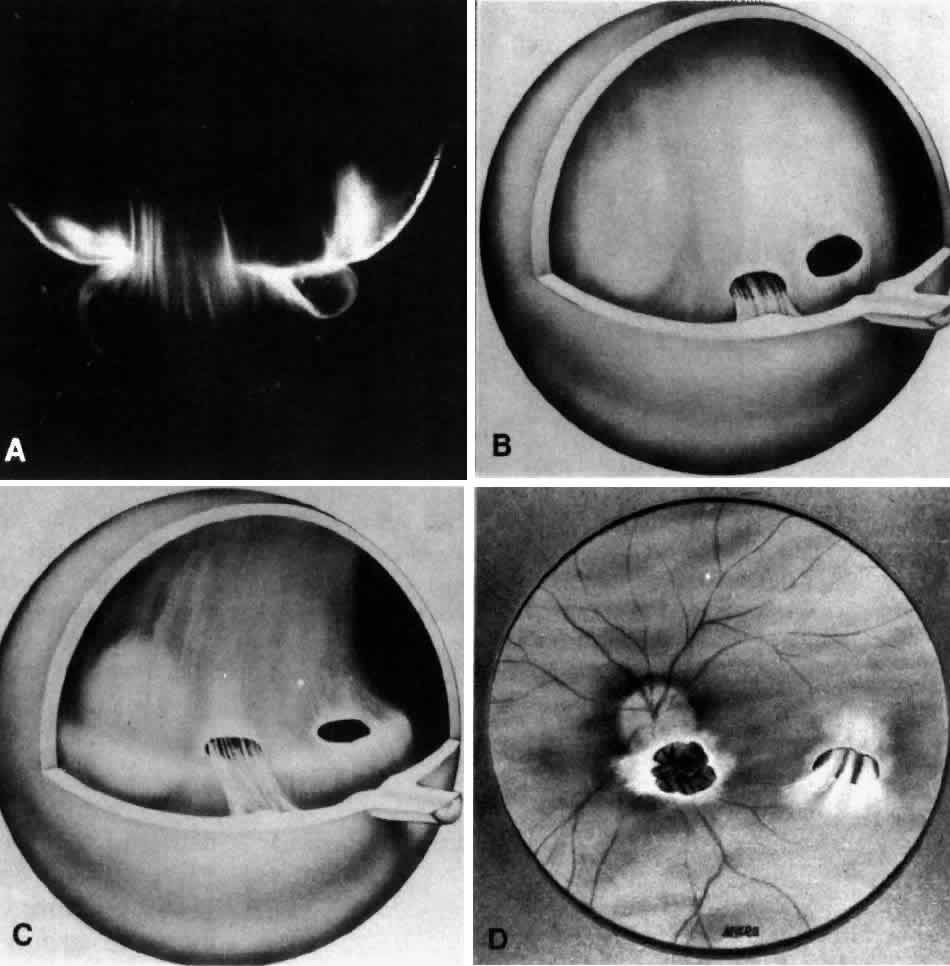

The posterior vitreous cortex is 100-110 μm thick50,60 and, as shown in Figure 12, consists of densely packed collagen fibrils.50,60,152 There is no vitreous cortex over the optic disc (see Figs. 4A AND 13), AND the cortex is thin over the macula due to rarefaction of the collagen fibrils.50 The prepapillary hole in the vitreous cortex can sometimes be visualized clinically when the posterior vitreous is detached from the retina (Fig. 14). If peripapillary glial tissue is torn away during PVD and remains attached to the vitreous cortex about the prepapillary hole it is referred to as Vogt's or Weiss's ring. Vitreous can extrude through the prepapillary hole in the vitreous cortex (see Fig. 4A) but does so to a much lesser extent than through the premacular vitreous cortex (see Figs. 4B AND D and 13). Jaffe153 has described how vitreous can extrude into the retrocortical space created after PVD and has proposed that persistent attachment to the macula (Fig. 15) can produce traction and certain forms of maculopathy.154,155 Although there are no direct connections between the posterior vitreous and the retina, the posterior vitreous cortex is adherent to the internal limiting lamina of the retina, which is actually the basal lamina of retinal Müller cells. The exact nature of the adhesion between the posterior vitreous cortex and the internal limiting lamina is not known but probably results from the presence of various extracellular matrix molecules.91 This concept is supported by studies156,157 in which vitreous cortex separation from the retina was induced using agents that acted on extracellular matrix components that could bind the posterior vitreous cortex to the internal limiting lamina of the retina.

Fig. 15. Anomalous posterior vitreous detachment. Vitreous can remain attached to the macula even in the presence of posterior vitreous detachment. In such cases, vitreous can extrude through the premacular vitreous cortex and fibers can insert into the macula. B, C, and D are an artist's rendition of this phenomenon. A demonstrates actual vitreous extrusion into the retrocortical space in a postmortem human specimen (see Fig. 4D) (B and C adapted from Jaffe NS: The Vitreous in Clinical Ophthalmology. St. Louis, CV Mosby, 1969; D adapted from Jaffe NS: Vitreous traction at the posterior pole of the fundus due to alterations in the posterior vitreous. Trans Am Acad Ophthalmol Otolaryngol 71:642, 1967)